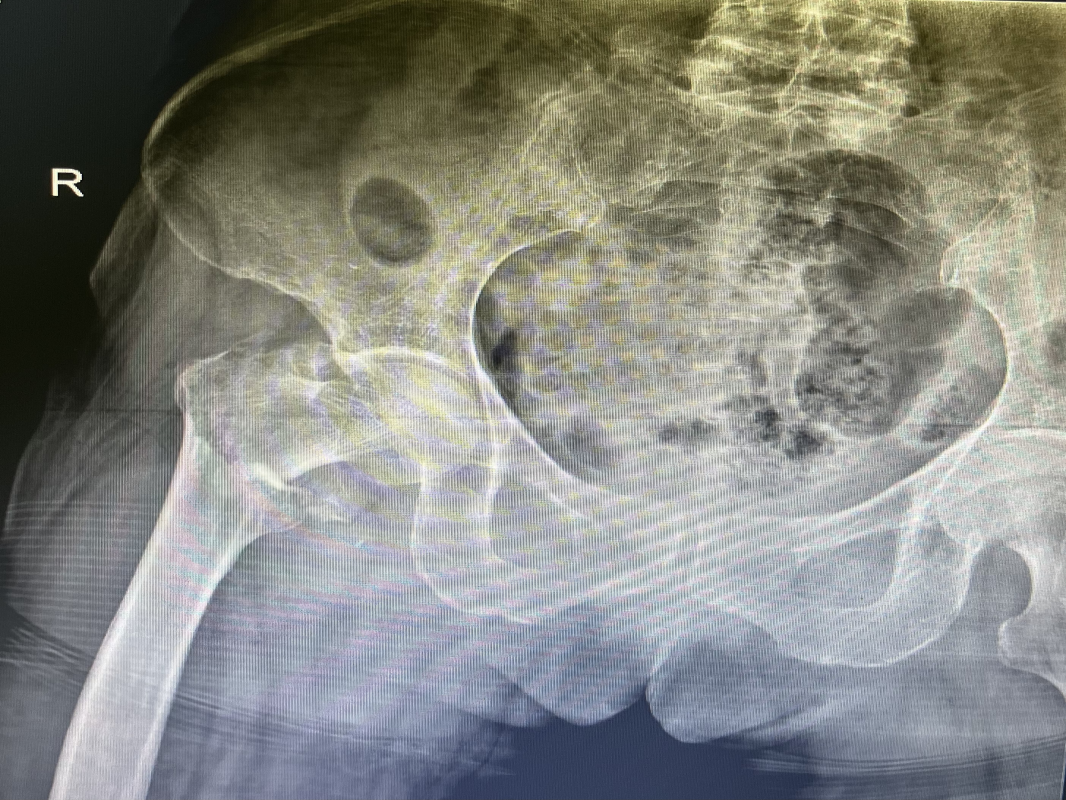

近日,我科收住一位高齡患者,孫某某,女,82歲,患者2小時(shí)前因摔傷致全身多處腫痛、伴活動(dòng)受限。入院后診斷:1.右股骨粗隆間粉碎性骨折;2.右尺橈骨遠(yuǎn)端粉碎性骨折;3.右鎖骨骨骨折;4.右肱骨大結(jié)節(jié)骨折;5.右恥骨下肢骨折;6.重度骨質(zhì)疏松。 鑒于患者屬高齡,損傷重,病情復(fù)雜,入科后科主任魏國(guó)華帶領(lǐng)關(guān)節(jié)骨科醫(yī)護(hù)團(tuán)隊(duì)積極完善相關(guān)檢查、科學(xué)制定治療方案,充分發(fā)揮中醫(yī)骨傷的治療優(yōu)勢(shì),保守與手術(shù)相結(jié)合,對(duì)右尺橈骨遠(yuǎn)端粉碎性骨折行手法復(fù)位石膏托外固定術(shù)。 排除手術(shù)禁忌后,在腰硬聯(lián)合麻醉下行右股骨粗隆間粉碎性骨折閉合復(fù)位PFNA內(nèi)固定術(shù),其余疾病行保守治療,術(shù)后經(jīng)活血化瘀、益氣養(yǎng)血等積極對(duì)癥治療,患者肢體功能恢復(fù)良好,已康復(fù)出院。 股骨粗隆間骨折是老年人常見(jiàn)損傷,俗稱人生最后一次骨折。老年人骨質(zhì)疏松,肢體不靈活,當(dāng)下肢突然扭轉(zhuǎn)、跌倒或使大粗隆直接觸地?fù)p傷,甚易造成骨折。由于粗隆部受到內(nèi)翻及向前成角的復(fù)合應(yīng)力,引起髖內(nèi)翻畸形和以小粗隆支點(diǎn)的嵌壓形成小粗隆蝶形骨折。亦可由髂腰肌突然收縮造成小粗隆撕脫骨折。粗隆部骨質(zhì)疏松脆,故骨折常為粉碎型。 就診地址:酒泉市中醫(yī)醫(yī)院關(guān)節(jié)骨科?? ?? 門診部:二樓205診室 住院部:綜合樓6樓住院部